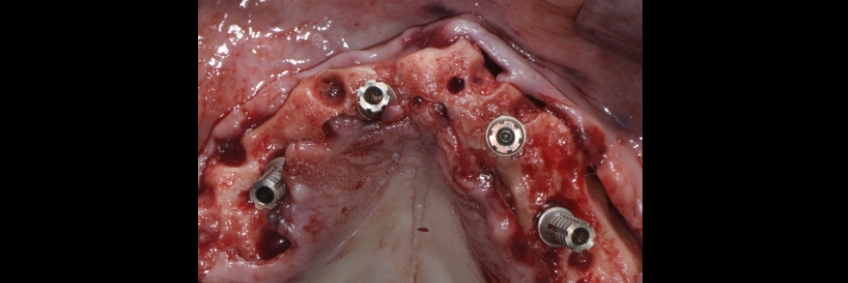

Often, during surgery, the treating team may choose a specific set of transmucosal or SRA abutments, as these vary in height and angulation (Straight, 17 degrees, and 30 degrees). The team then fabricates the provisional restoration and waits for the implants to be fully osseointegrated prior to fabricating the definitive prosthesis.

This visual essay shows, through a series of images, the fabrication of a maxillary implant-supported fixed dental prosthesis. The SRA abutments of the anterior implants were changed to optimize the definitive implant-supported fixed dental prosthesis design.